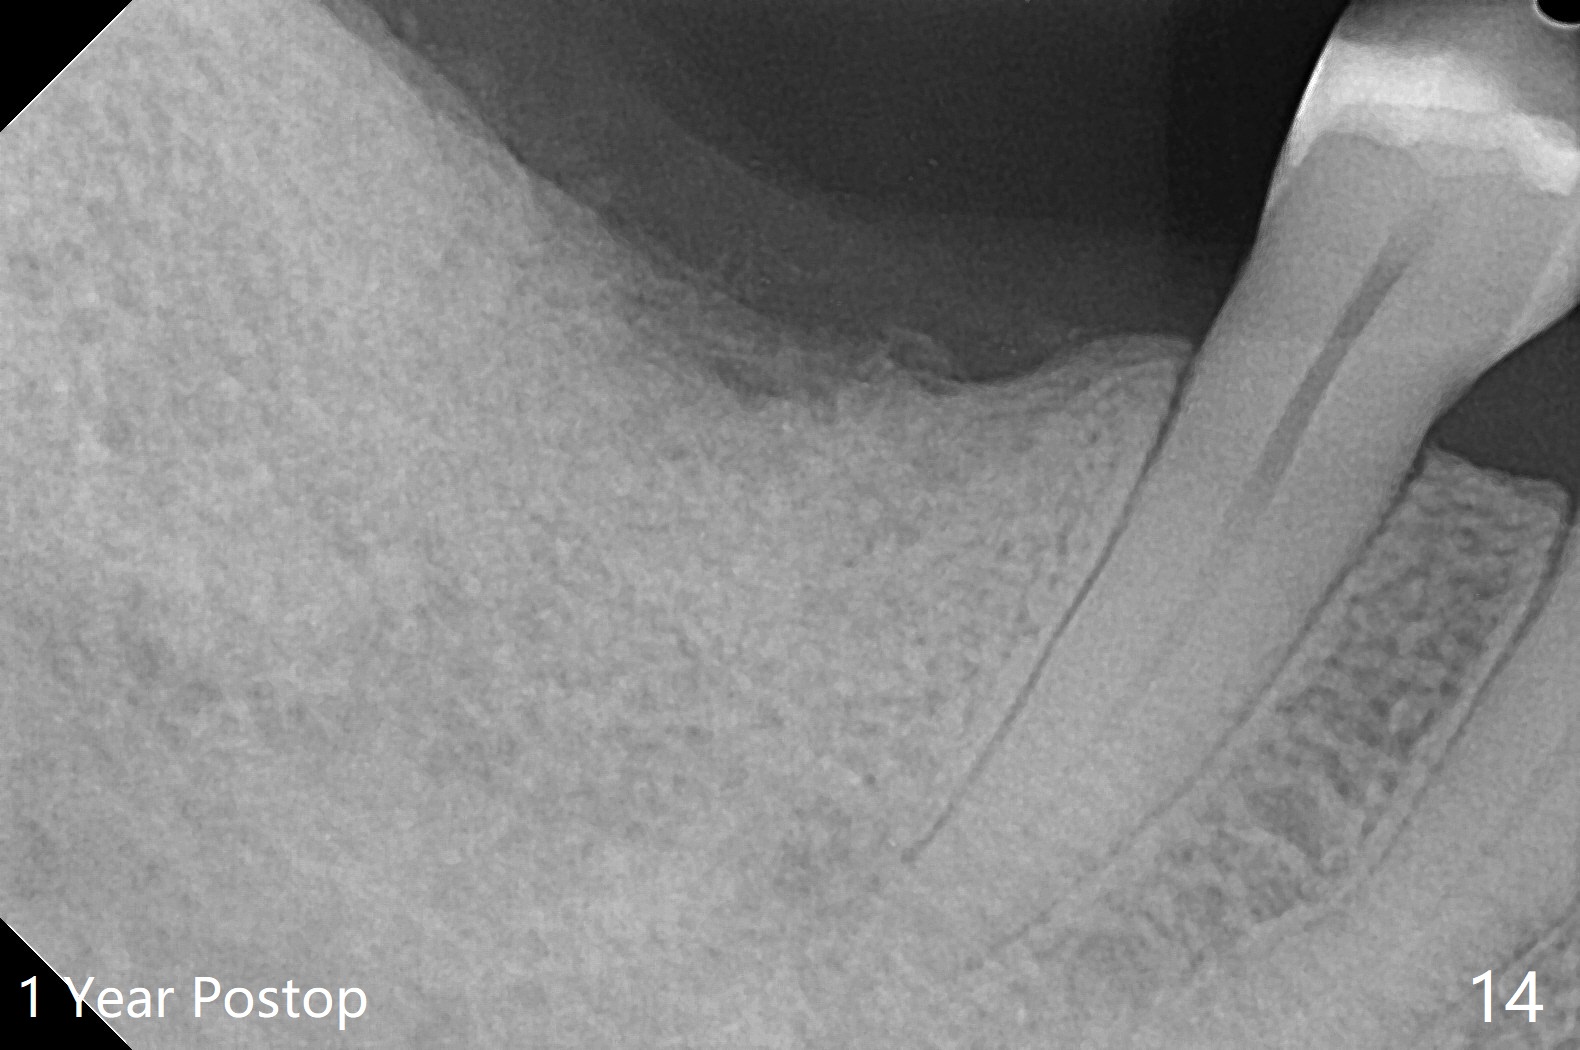

There are signs of periimplantitis at #30 eleven months postop (Fig.1 (* bone loss)). The bony defect (Fig.2) will be filled with allograft mixed PRF liquid to form sticky bone (Fig.3,4), followed by PRF membrane (not shown) and a piece of 6-month membrane (Fig.5). A hole is cut so that the 6-month membrane can slide down the abutment (Fig.2,5 A) to cover the bone graft around the implant (Fig.2,7 I). Setting acrylic is applied around the abutment and neighboring teeth for further protection and holding (Fig.8). The periimplantitis does not resolve nearly 7 months post graft. The implant will be removed. Prepare UF extra wide kit and try to insert 6.5 or 7.0 mm tap. Also prepare sticky bone and Cytoplast for wound closure. Implant removal involves surgical handpiece, 6.2/7 mm trephine bur, elevators, and implant driver. The defect is large (Fig.9) with the low buccal crest (Fig.10) and bone graft with PRF ("sticky bone") is placed, covered by PRF and 6-months membrane (Fig.11). The next implant will be placed with guide. If oral hygiene is not ideal, choose a bone level implant. The middle of the wound dehiscences slightly 8 days postop (Fig.12), accounting for mild loss of bone graft 1 year postop (Fig.14). The keratinized gingiva is apparently wide 1 year postop (Fig.13). There is mild loss of bone graft in the middle of the superficial area (Fig.14). The buccal plate seems to regenerate 1 year postop (pandemic delay, Fig.15).